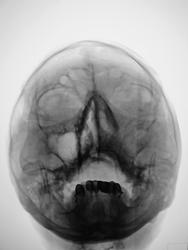

похоже на гиперпластический. В лобной пазухе виден уровень жидкости.

А я плохо вижу костные стенки левой гайм. пазухи...."оно" проростает..

Согласен, невиден медиальный контур левой гайморовой пазухи, надо исключить деструкцию

затемнение не совсем гомогенное, возможно солидные образования в верхнечелюстной пазухе. Во фронтальной не вижу достоверных данных за уровень-что можно было бы трактовать за жидкость. Для этого надо уточнить положение пациента при исследовании, а так же рентгенография пазух лобной кости в боковой проекции в вертикальном положении пациента. Имея только этот снимок - Левостороний гемисинусит. А вообще рекомендовал бы томографию, ну честно-все встало бы на места.

Снимок сделан в вертикальном положении.